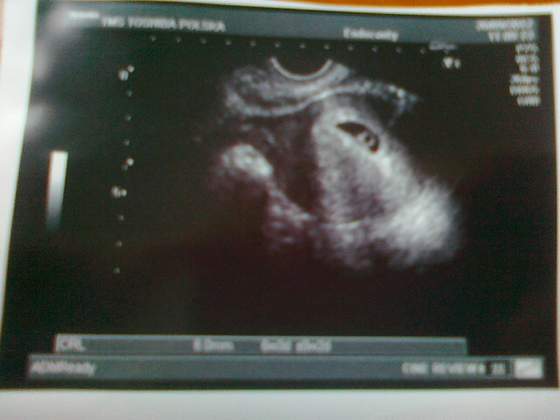

Pani gin powiedziała mi, że teraz do 12 tyg to taki średni przyrost to będzie ok 1-3,5 mm dzienne